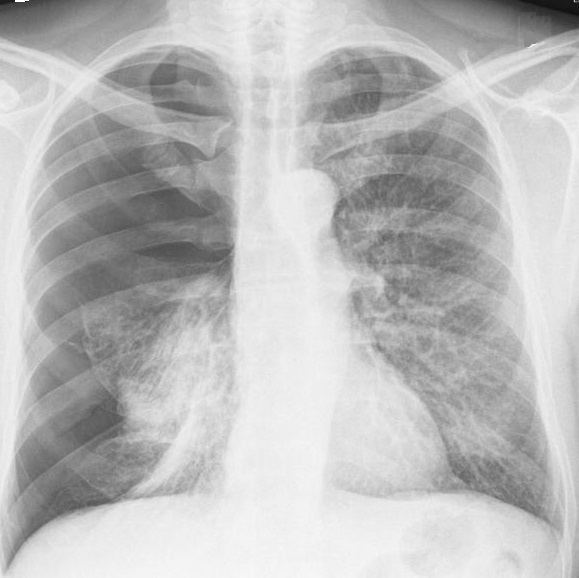

Aspect

radiologique d'une pneumothorax à petit

volume du pomon droit . Cliche de face

PA en inspiration |

|

Meme cas à

exposant au temps de expiration . On

peut en s'observe le pneumothorax à

petit volume collecte à l'apex et à

region axillaire droit du poumon |